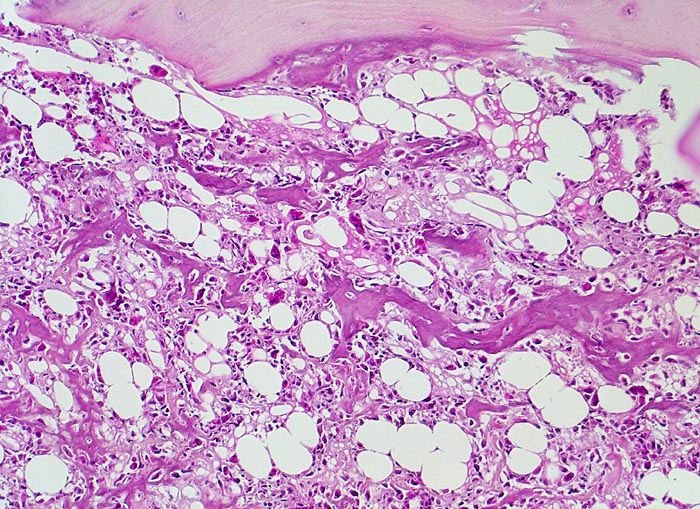

Morphologische Merkmale:

• Tibiametaphyse mit angrenzendem Weichteilgewebe.

• Das Sarkom infiltriert diffus den spongiösen Knochen der Diaphyse und hat präexistente Knochenbälkchen verdrängt.

• Der Tumor hat die Korticalis destruiert und infiltriert die angrenzende Skelettmuskulatur.

• Der Tumor besteht aus neugebildetem bereits verkalktem Knochen oder einem Netzwerk von primitiven Osteoidtrabekeln. Entlang oder innerhalb der Osteoidtrabekel lokalisierte polymorphe Tumorzellen mit ausgeprägten Kernatypien und zahlreichen Mitosen. Leicht verwaschene Kernstrukturen als Folge der Gewebsentkalkung.